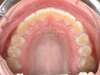

Cas 3 : Description

Encombrement aux deux arcades.Traitement par gouttières.

Avant

Après